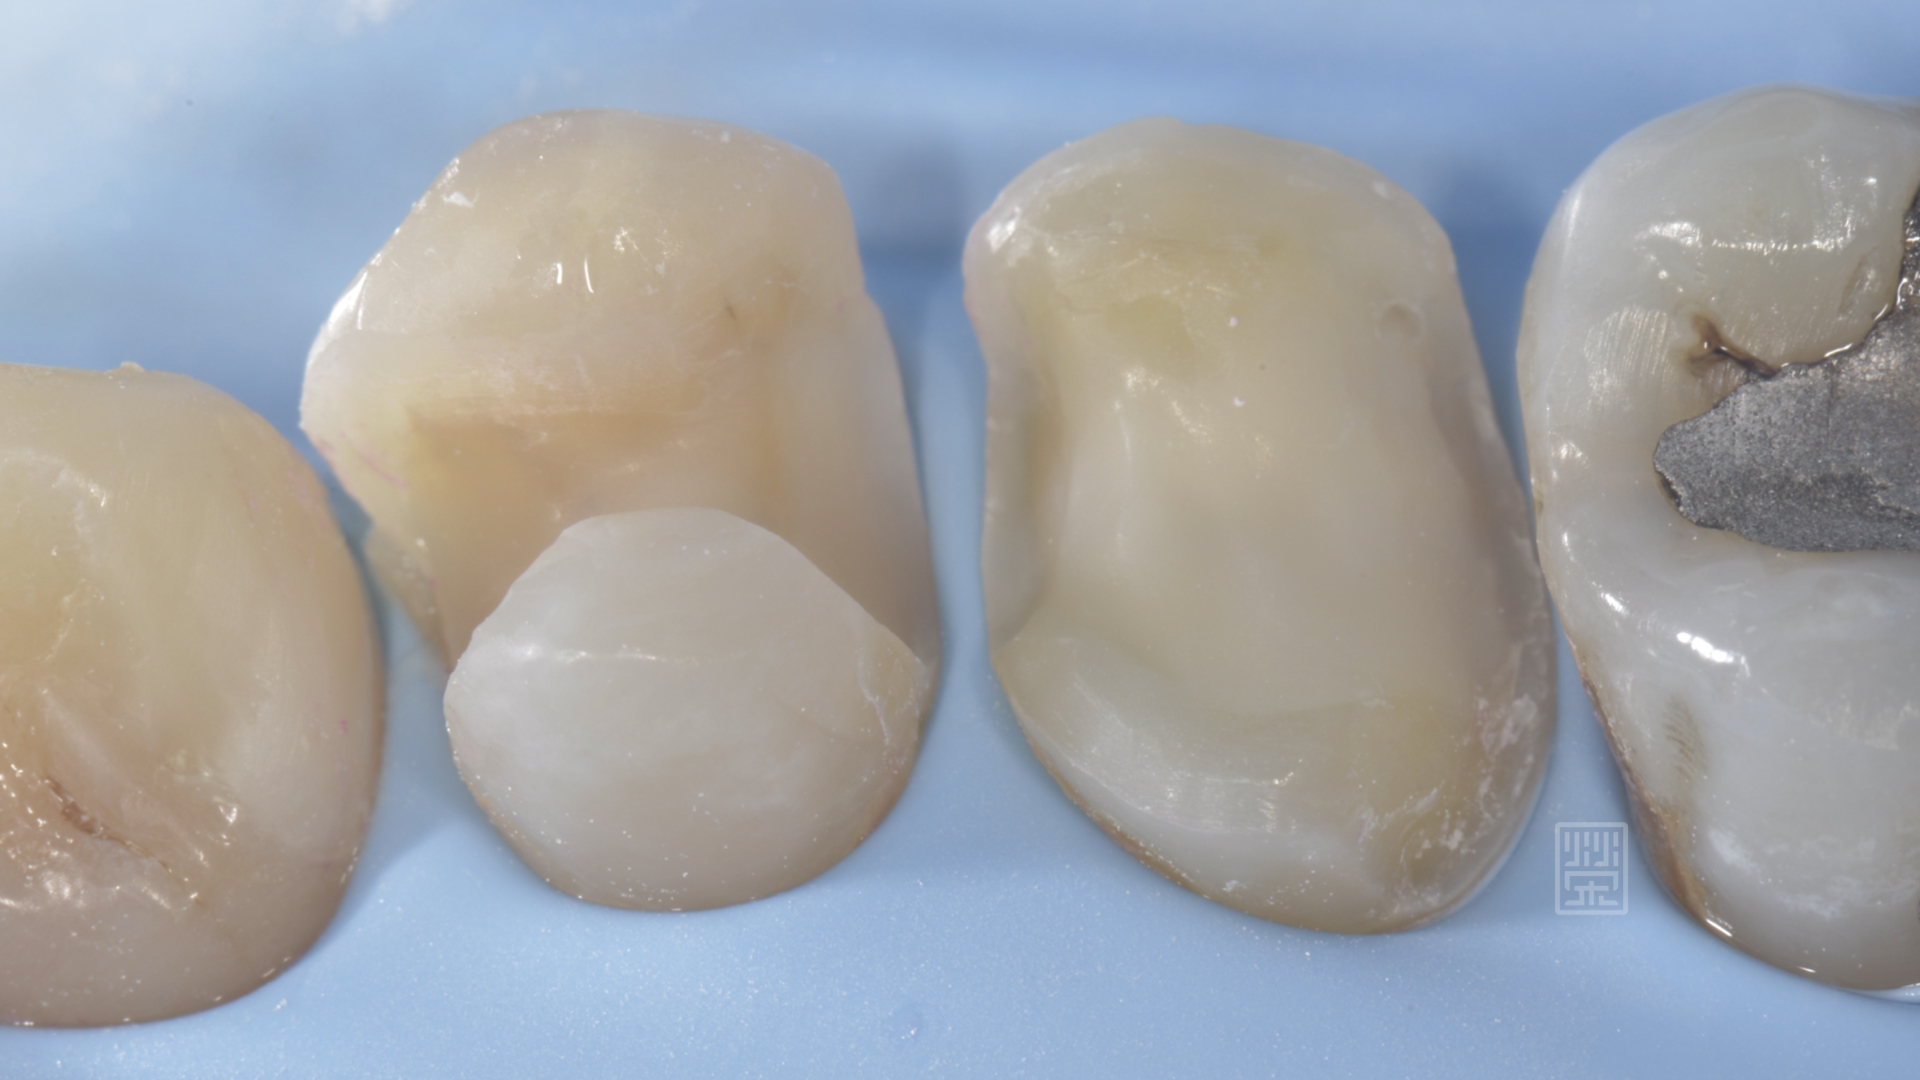

對於牙齒脆弱的部分,做包覆性保護牙齒

紅色是齒質,只做1mm空間修復,藍色部分是蛀牙至牙齦處,修磨至牙齦處